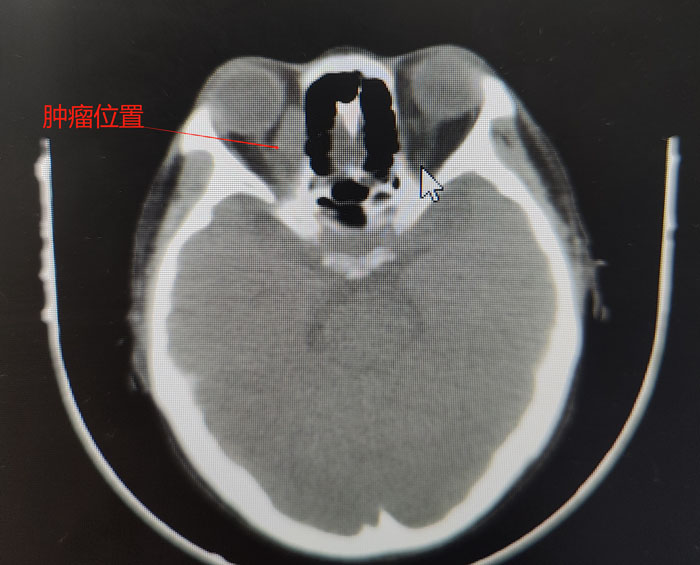

患者的病情非常特殊,其眼眶肿物内下方距离眶缘1cm处有一根较大的动脉血管,而肿瘤内侧又紧挨着眼球,一旦穿刺出血,在患者血小板及白细胞危急值的状态下开眶止血,无疑是难上加难。其次,术后暴发感染的风险也难以控制。同时,穿刺是为了更好地明确病理,需要选用粗针,这又极大增加了穿刺风险……面对如此复杂的形势,在眼科肿瘤团队和纪晓惠主任医师的配合下,确定穿刺位置和进针方向、深度,经过三次“惊心动魄”的穿刺,顺利取出三条鱼肉状肿物组织,病理诊断后,疾病的“真容”终于露出水面,患者确诊为非霍奇金弥漫大B淋巴瘤。噬血细胞综合征考虑为淋巴瘤继发,需要积极控制淋巴瘤原发病。之后,患者前往我院血液中心接受进一步规范化精准治疗。